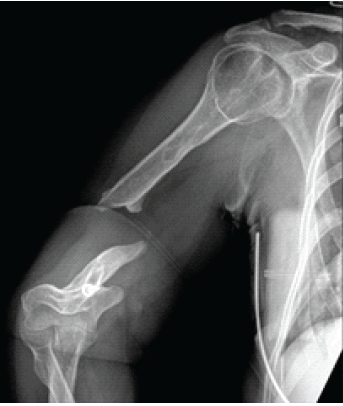

A Humeral Shaft Non-union Treated With Proximal Tibia Cancellous Autograft and Fibular Strut Allograft: A Case Report

P Tantone Ryan , SeHoon Park , Greco Victor

………………………………p.112-116